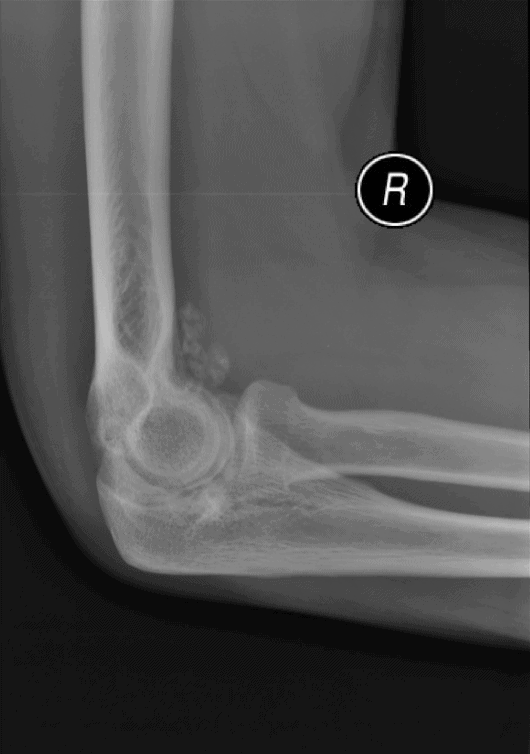

U sụn màng hoạt dịch

» Thông tin: Nữ giới – 32 tuổi.

» Lâm sàng: Đau khuỷu tay 2 năm.